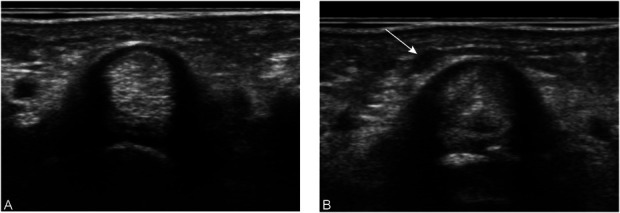

背景:屈肌腱鞘神经节(FTSG)形成的确切机制尚不清楚。我们假设向A1滑轮注射类固醇是FTSG的原因之一。因此,本研究旨在评估狭窄性屈肌腱滑膜炎患者注射类固醇后发生FTSG的风险。方法:这项前瞻性队列研究纳入了2019年8月至2024年5月期间诊断为狭窄性屈肌腱滑膜炎的患者。114名过去6个月内没有注射史的患者共有128根手指同意参与这项研究。对A1滑轮进行初始超声检查,排除已有FTSG的患者。注射组根据患者喜好,在屈肌腱鞘内注射类固醇(曲安奈德5 mg + 1%利多卡因0.5 ml), 3个月随访超声。对照组在同一时间点行超声检查,不注射。结果:注射组53指(43例),对照组22指(21例),随访3个月超声检查。注射组53个手指中有20个(37.7%)发生FTSG,而对照组22个手指中有1个(4.5%)发生FTSG。风险差异为0.33(95%可信区间:0.18-0.49;p < 0.01)。注射组症状改善率为93%,对照组为45%,差异有统计学意义(p < 0.01),说明注射组症状缓解更明显。结论:本研究认为,类固醇注射治疗狭窄性屈肌腱滑膜炎引起的小穿刺可导致FTSG;然而,神经节形成的临床意义还需要进一步的研究来充分阐明。证据等级:二级。有关证据水平的完整描述,请参见作者说明。

Results: Three-month follow-up ultrasound evaluations were conducted on 53 fingers (43 patients) in the injection group and 22 fingers (21 patients) in the control group. The incidence of FTSG was significantly higher in the injection group, with 20 of 53 fingers (37.7%) developing FTSG compared with 1 of 22 fingers (4.5%) in the control group. The risk difference was 0.33 (95% confidence interval: 0.18-0.49; p < 0.01). Symptom improvement was observed in 93% of the injection group compared with 45% of the control group (p < 0.01), indicating more significant symptom relief in the injection group.